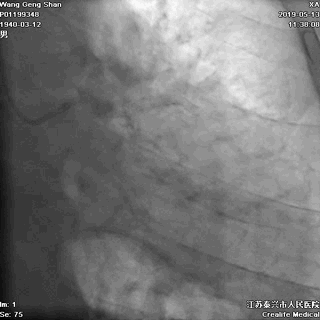

06 LM-LAD支架后扩张

交换回旋支导丝,非顺应性球囊顺序高压扩张

07 LM支架近段优化(POT)

左主干近段用大一号非顺应性球囊行高压扩张

IVUS评估,支架贴壁良好。